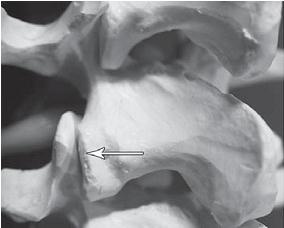

Фото № 3. На фото макета позвоночника стрелкой указан дугоотростчатый сустав позвоночника.

Дугоотростчатые суставы имеют синовиальную оболочку, фиброзную капсулу, суставную полость с синовиальной жидкостью, связки. Каждый дугоотростчатый сустав покрыт гиалиновым хрящом, по краю которого (на расстоянии 2–4 мм от края сочленяющихся поверхностей) прикрепляется капсула сустава. Изнутри суставная капсула покрыта синовиальной оболочкой. По передней поверхности она покрыта желтой связкой и составляет заднюю поверхность межпозвонкового отверстия. Капсула усиливается дорсально за счёт многораздельных мышц и вентрально жёлтой связкой, которая вплетается в неё в верхнемедиальном отделе. Верхний суставной отросток лежащего ниже позвонка массивнее нижнего и расположен больше кпереди и кнаружи, а нижний — кзади и кнутри. Часть верхнего суставного отростка у корня дуги участвует в формировании бокового углубления позвоночного канала.